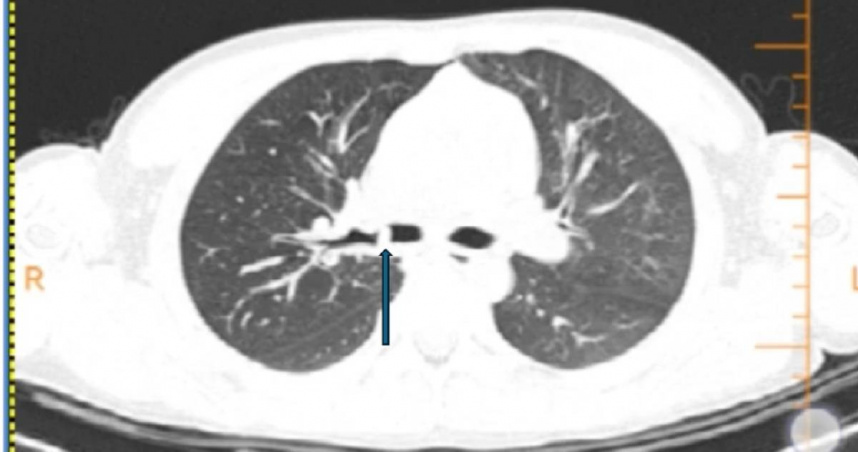

據陸媒《極目新聞》報導,近日樂樂在吃豬腳時突然發生嗆咳,當時咳得滿臉通紅,但未咳出異物。隨後數天,樂樂的咳嗽不僅愈發加劇,甚至出現血痰及呼吸困難現象。家長帶他到當地醫院檢查,CT顯示樂樂右主支氣管有可疑陰影,且右肺出現肺氣腫,病情複雜,家長隨即轉送至廣州醫科大學附屬婦女兒童醫療中心急診科。

呼吸科醫師楊迪元詳細審閱CT後,發現樂樂肺部的陰影位置異常,懷疑並非典型異物。在追問病史時,家長才回憶起半年前樂樂曾因誤吞糖果包裝紙嗆咳,當時症狀劇烈但自行緩解,因此未就醫檢查。